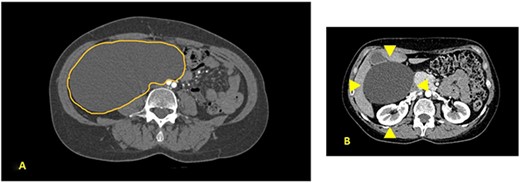

A 52-year-old female was visited at our outpatient service on November 2021 for increasing back pain (4.5 points in the Pain Scale Chart) and the presence of a huge palpable mass occupying the entire right abdomen; she complained of a decade history of recurrent abdominal pain and repeated ultrasound (US), revealing an increasing abdominal cystic-like bulk with fluid content (18 × 8.5 cm. at last US). Neither previous abdominal surgery nor significant familiarity was referred; canalization and food intake were described as regular. At physical examination, a large mass occupying right abdomen could be easily detected; basic laboratory panel and tumoral markers were within range, while body mass index and KPS were, respectively, 21.2 and 90%. Angio-computed tomography (CT) scan revealed a ‘Gross oval-shaped mass with clear fluid content (10–15 HU) and regular margins, measuring 15 × 10 cm. in maximum axial diameter and cranio-caudal extension of ~20 cm, surrounded by a thin hyperdense wall in the absence of intralesional enhancement on delayed phase’ (Fig. 1A). Several structures were displaced as an effect of tumoral enlargement (lower aspect of the right kidney, inferior vena cava, right psoas muscle, gallbladder, right ascending colon, some jejunal loops, head of the pancreas and common bile duct; Fig. 1B). The entire right abdomen resulted as occupied by this huge cystic lesion, which caudally reached the homolateral iliac space. At Prohance® MR, both T1- and T2-weighed sequences confirmed main radiological findings (size 15 × 20 cm, thin aspect of envelope, absence of infiltrative aspect and gross displacement of surrounding structures; Fig. 2A–C). On these bases, preoperative diagnosis of simple mesenteric cyst was hypothesized and the patient was addressed to surgical treatment. Hybrid open-laparoscopic approach was planned: peritoneal space was reached via a midline of 4-cm supraumbilical access and a wall protector-retractor device (Alexis®—Applied Medical) was positioned. Cystic wall lied just beneath surgical access: after a 2/0 Vicryl 2/0 purse string, cyst was incised and 1600 ml of clear-watery content was removed and sent for cytology. Cystic envelope was sharply dissected from ascending colon (Fig. 3A) and was reintroduced into the abdomen. After closing the Alexis® device, a 12-mmHg pneumoperitoneum was induced with the positioning of the 10-mm Alexis® trocar and 2 5-mm working cannulas. Deepest aspect of the cystic wall was completely dissected from the hepatic flexure of the colon and from the second duodenal portion by using a US device and the specimen was removed and sent for histological examination (Fig. 3B). Post-operative was uneventful and the patient was discharged on the second post-operative day. Cytology result was negative for malignancy; at histological examination, a thin-walled cystic formation, translucent at macroscopical appearance was described. Maximum diameter of the empty lesion was 15 cm. Definitive diagnosis was ‘simple serous cyst of the mesentery’ (IHC staining Calretinin−; CD10−).

(A) Contrast CT scan; gross oval-shaped mass with clear fluid content (10–15 HU) and regular margins, measuring 15 × 10 cm in maximum diameters; (B) evidence of liver and gallbladder compression (arrowheads).